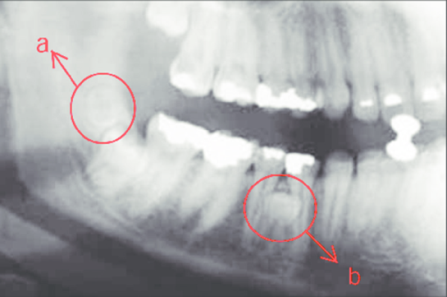

Răng thừa (b) mọc trong vòm miệng khiến cho R22 (a) mọc lệch xoay trục XQ răng toàn cảnh không thấy răng thừa do R21 (a) che khuất,(b) là R22 bị xoay trục

Hình ảnh răng thừa (a) xuất hiện rất rõ trên CT Cone Beam, (b) là hình ảnh R21

Hình 3: Tính ưu việt của CT Cone Beam trong chẩn đoán răng thừa

(Nguồn: Bệnh viện Đa khoa Tỉnh Quảng Trị)